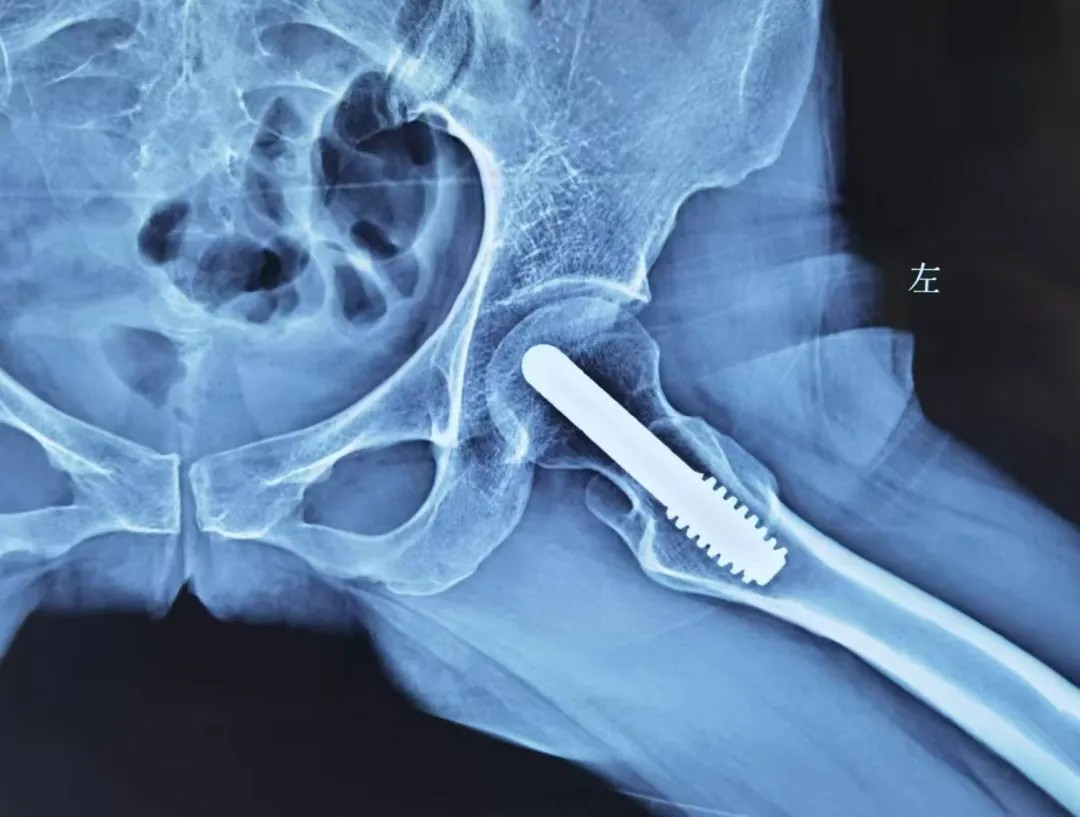

中(zhong)期:微創 “救” 股骨頭

股骨頭壞死中(zhong)期,此時股骨頭開始出現(xian)小(xiǎo)裂縫但沒塌陷,可(kě)以(yi)做微創保髋手術(shù),比如 “髓芯減壓術(shù)”(鑽小(xiǎo)孔減輕股骨頭內(nei)壓力(li))、“植骨術(shù)”(填入新(xin)骨促進(jin)修複),術(shù)後(hou)配(pei)郃(he)康複訓練,盡可(kě)能(néng)保留股骨頭功能(néng)。

若股骨頭塌陷輕微,還能(néng)嘗試 “截骨術(shù)”(調整股骨頭受力(li)位置);或采取钽棒置入術(shù),即在(zai)股骨頭中(zhong)放入钽棒,支撐壞死區(qu)域(yu)。